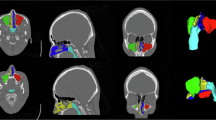

The nasal cycle refers to the periodic alternation of congestion and decongestion between the two nasal passages, a process that can be visualized with CT and MRI imaging. These coronal sections of the nasal cavity show dilation of the left nasal passage and constriction of the right, indicating left-side dominance and greater airflow through the left passage at the time of imaging.